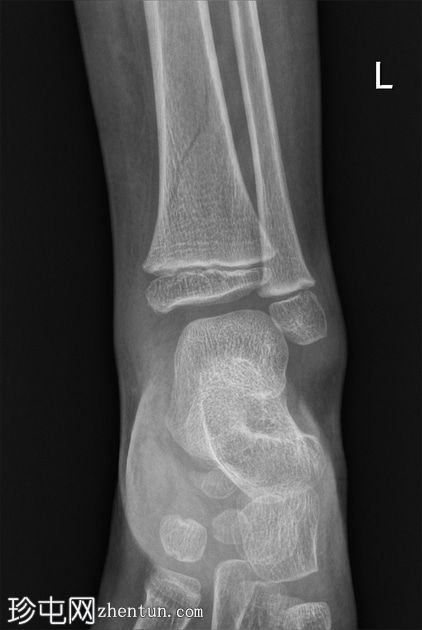

左腿及踝关节

X线片

正位

斜位

胫骨远端骨干可见一条螺旋状透亮线,提示骨折(正位、侧位)。

幼儿骨折是指幼儿因扭转(足部着地时股骨内旋)导致的胫骨中远端轻微移位的螺旋状骨折,这种情况可能发生在儿童绊倒时。患者接受了6周的石膏外固定治疗。